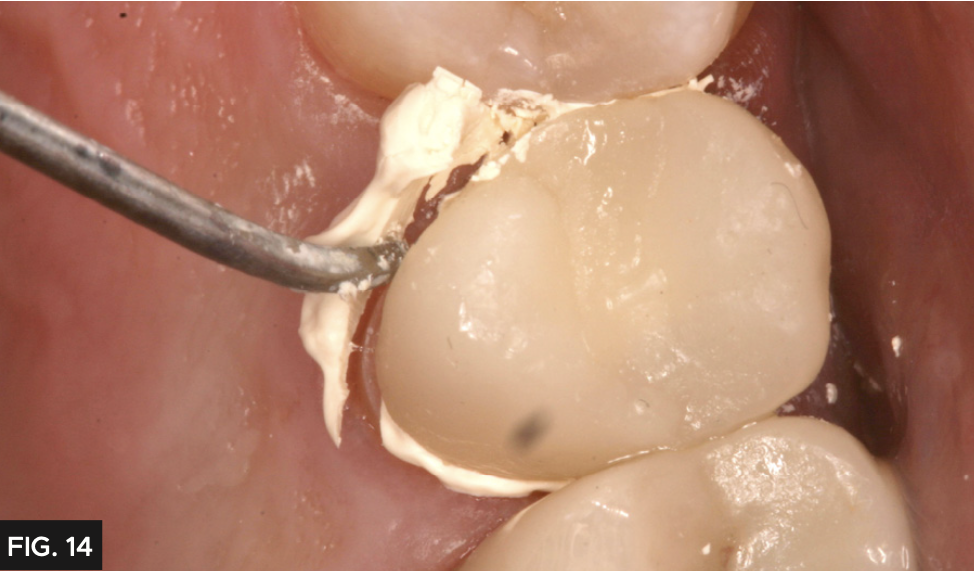

A common clinical problem with provisional restorations is premature dislodgement, which is frustrating for the patient and results in a costly repair appointment. For added retention, the crown was cemented with Cling2® (Clinician’s Choice®). Cling2 has a more retentive chemistry to prevent loss of the provisional before the seating appointment. The provisional was loaded with Cling2 (FIG. 13) and placed over the preparation and allowed to set for two minutes. The excess was easily removed with a curette. (FIG. 14) It is common to have excellent tissue health at the final cementation as Cling2 has a bacteriostatic effect.